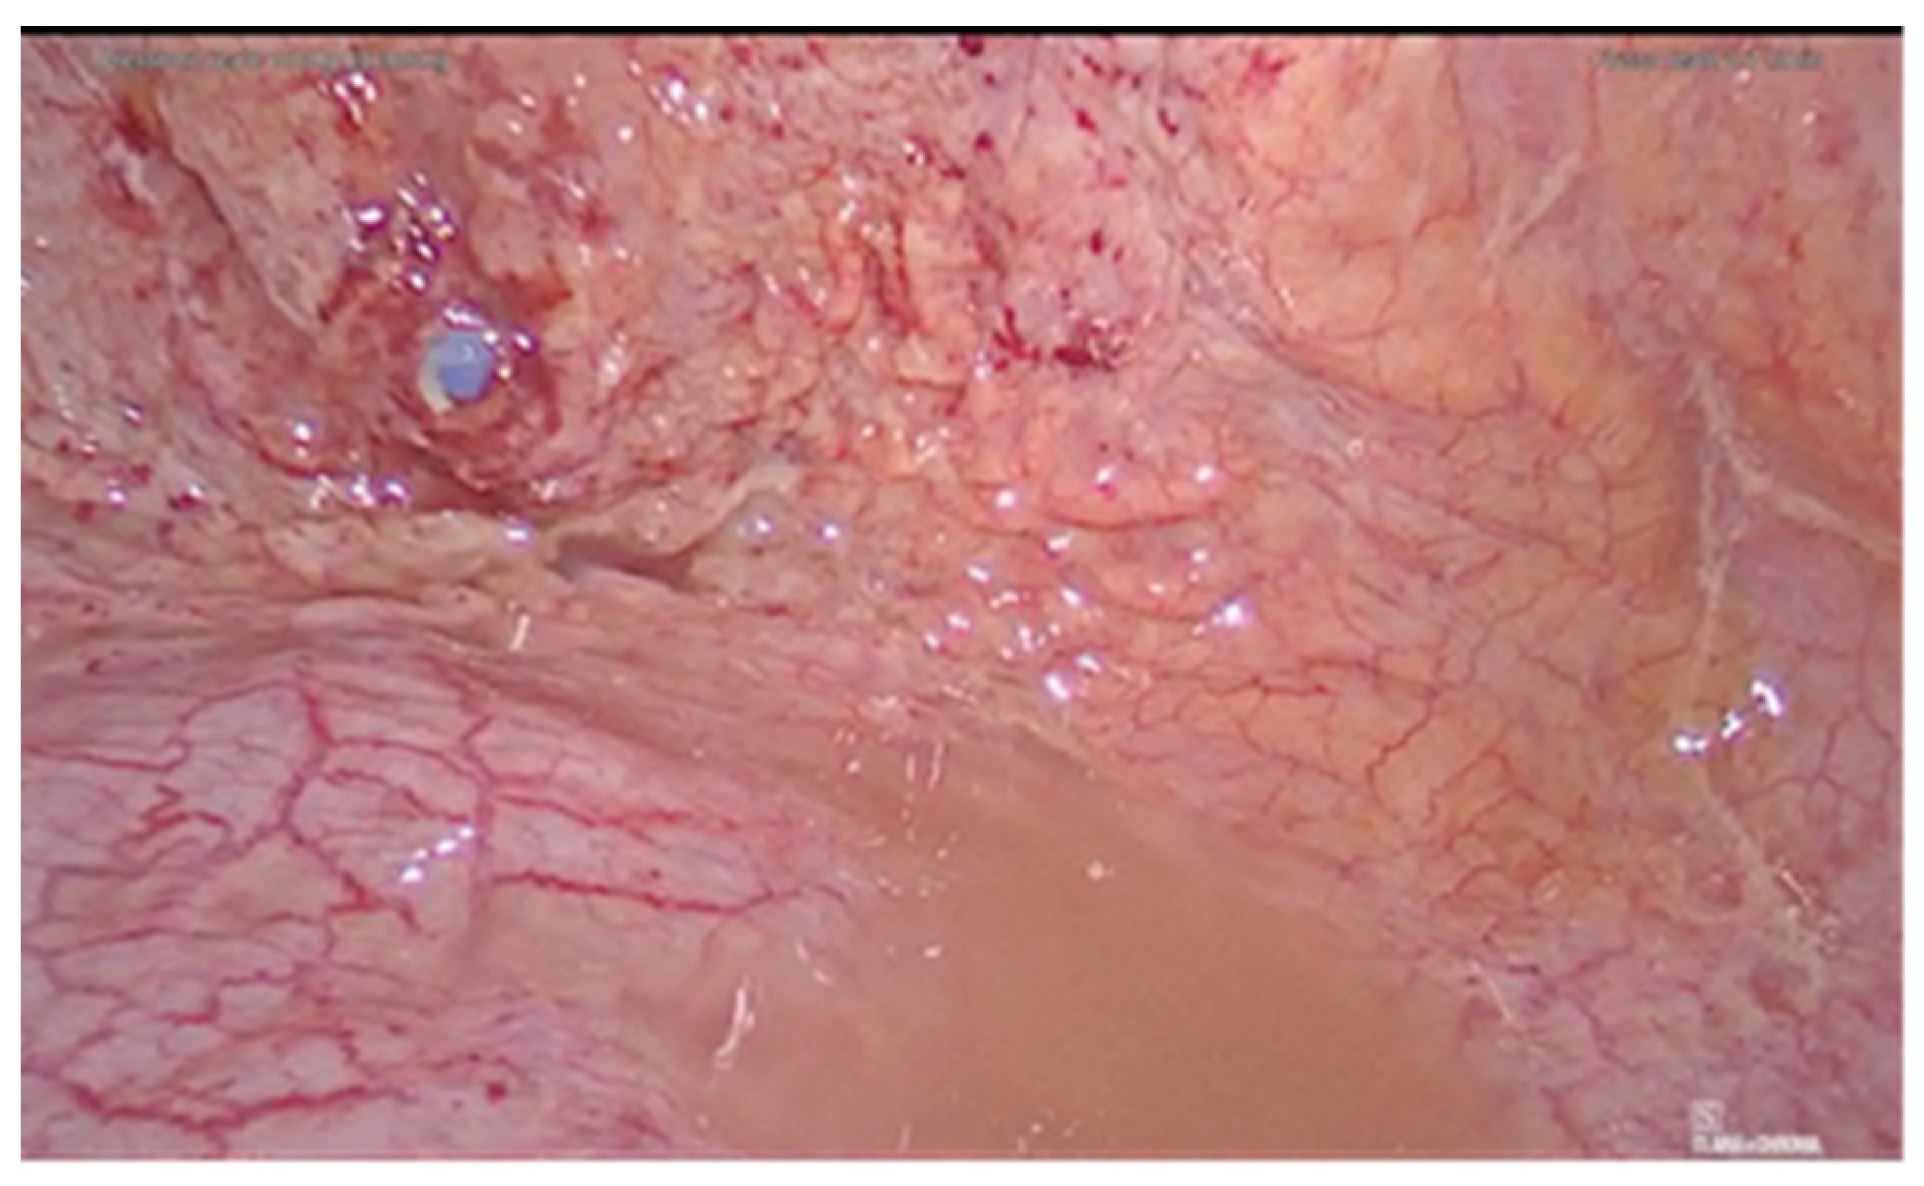

2. Case